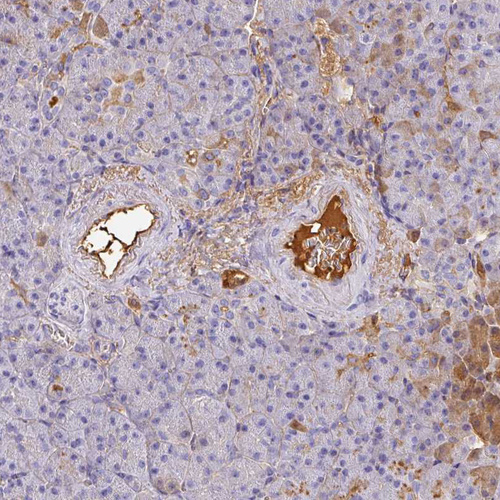

Immunohistochemical staining of human kidney, pancreas, placenta and prostate using Anti-ALB antibody HPA031025 (A) shows similar protein distribution across tissues to independent antibody HPA031024 (B).